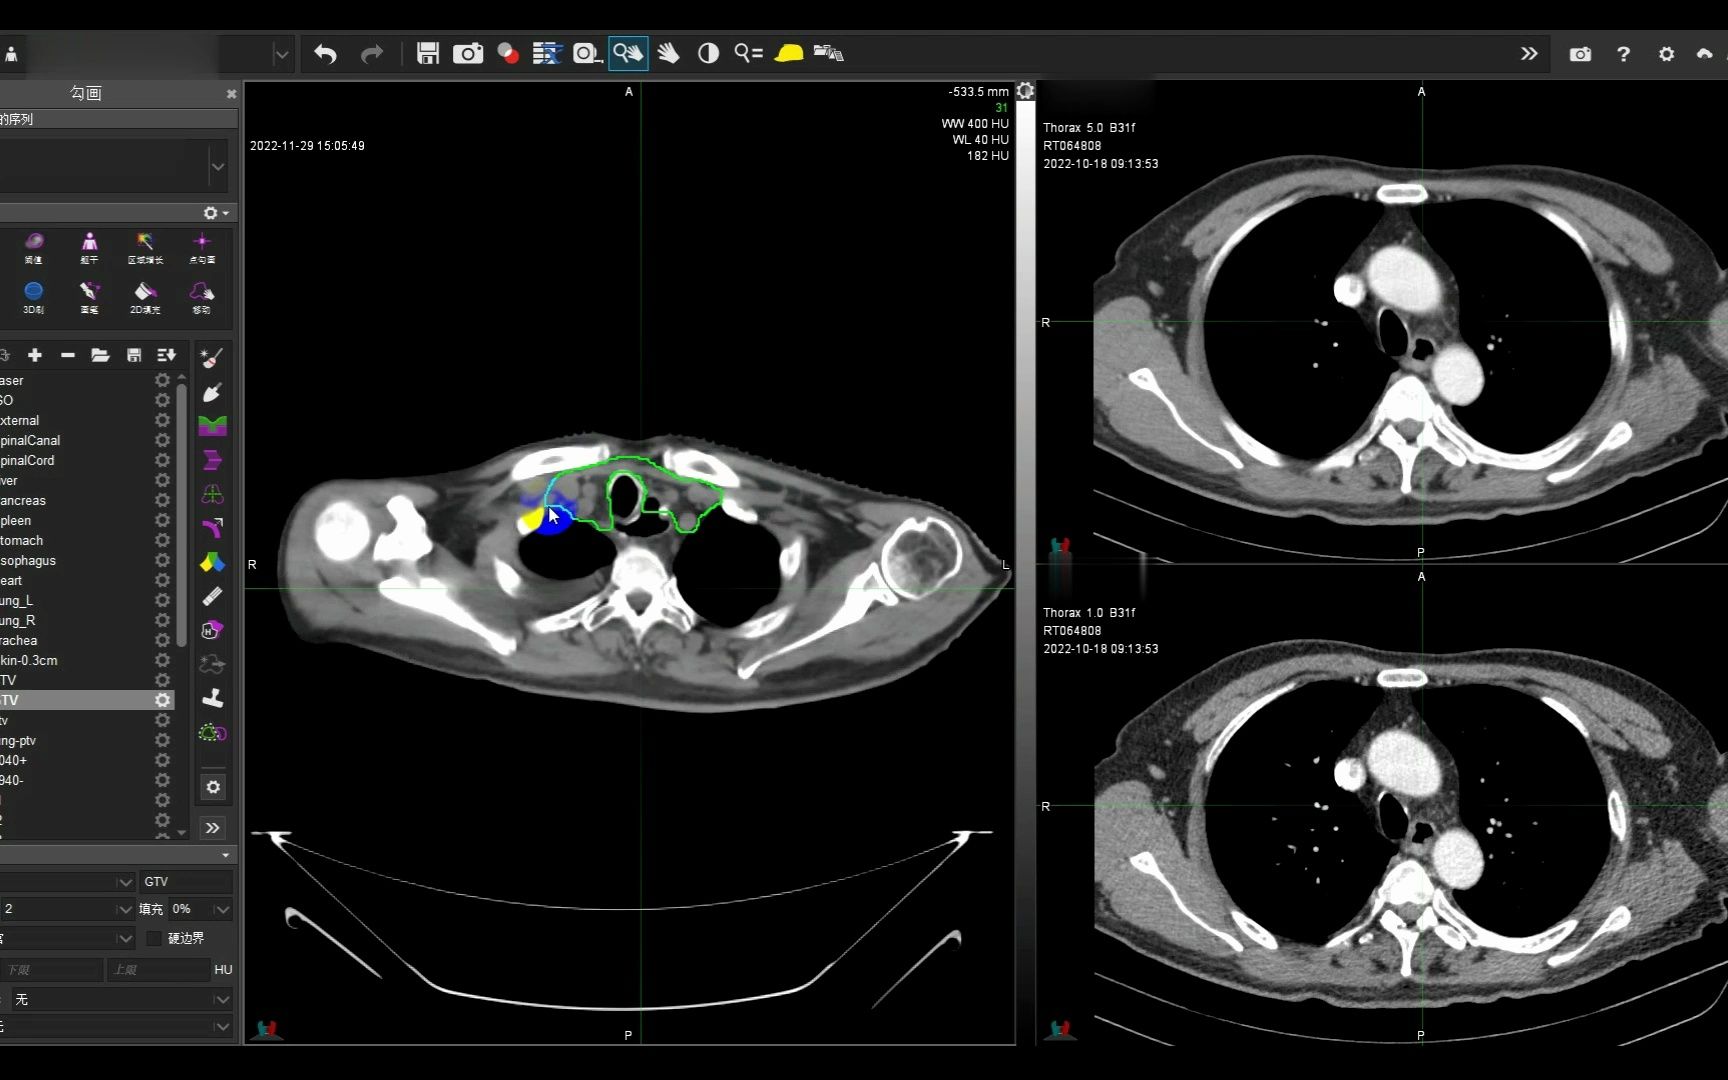

食管癌术后放疗靶区勾画

图片尺寸1728x1080